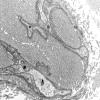

PERIPHERAL NEUROPATHY

4 AXONAL DEGENERATION

3 Electron Microscopy (6)